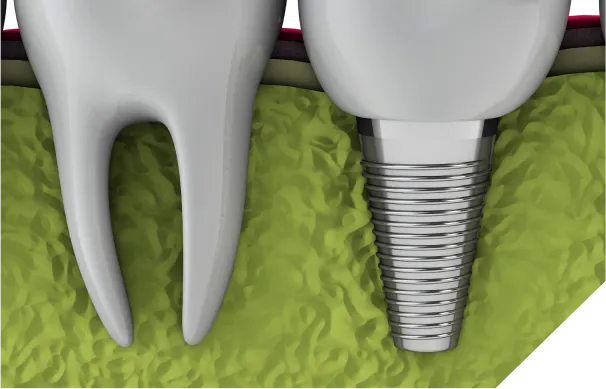

インプラントは、自分の歯のような見た目と噛み心地といったメリットがありますが、反面、手術を必要とする治療法です。インプラントに限らず、どんな医療行為にも100%安全ということはなく、インプラント治療にも様々なリスクや注意点が存在します。

骨との結合が

うまくいかない事故埋め込んだインプラントが顎の骨と結合しない(オッセオインテグレーション不全)と、インプラントが固定されず、最終的に撤去せざるを得ないリスクがあります。

骨の厚みや高さの不足

歯を失ってから時間が経つと、顎の骨が痩せてしまい、インプラントを支えるための十分な厚みや高さがなくなることがあります。無理に埋入すると、安定せず脱落するリスクがあります。